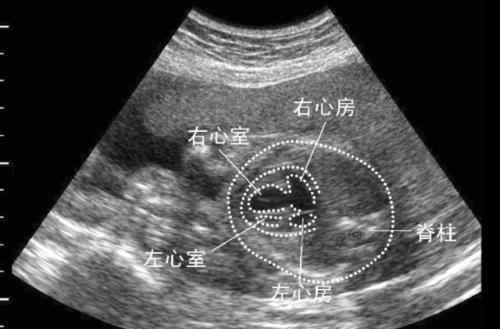

28周胎儿超声心动图检查左心室强光斑